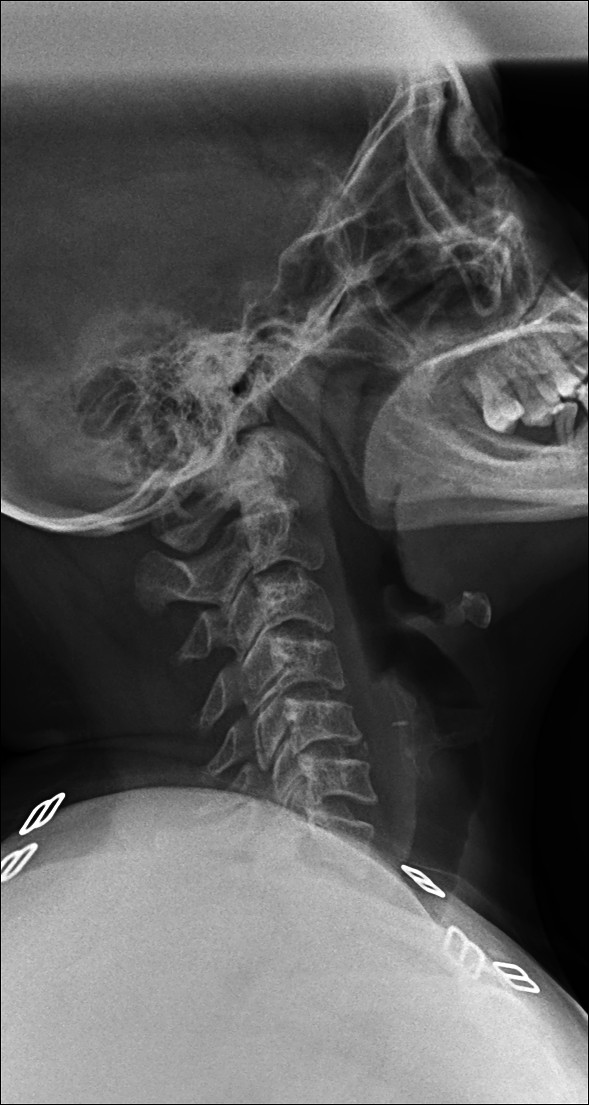

Cervical Spasm

Straightening of cervical spine (Loss of cervical lordosis)